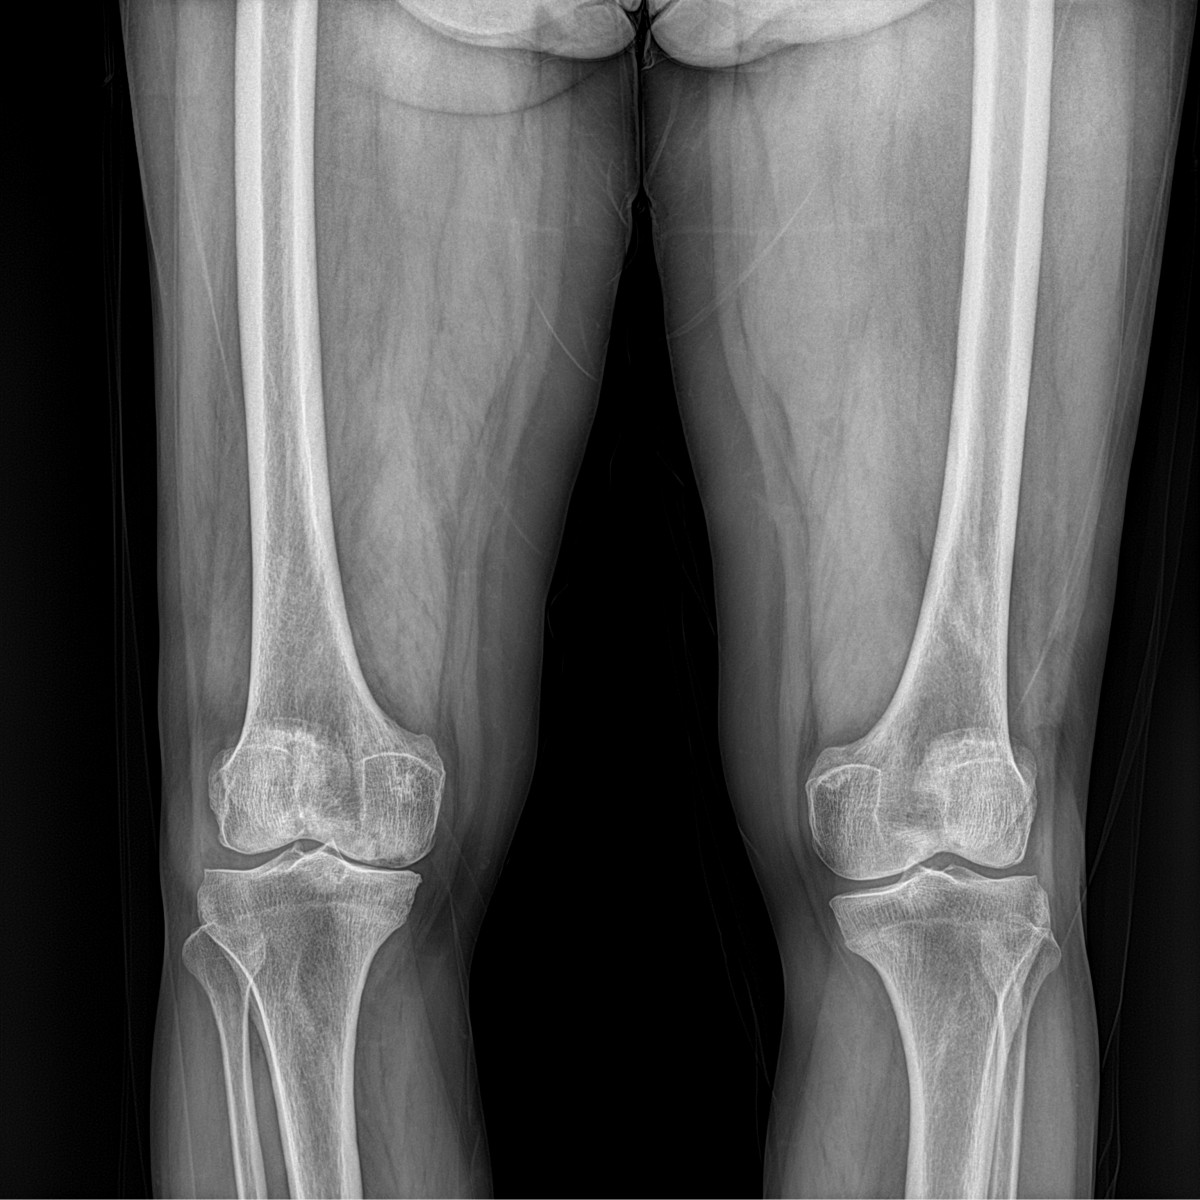

이재상원장님 무릎 인공관절 치환술 이영O 환자

dae765e4d9ac96aee867c9d6292d8784_1758010542_2461.jpg